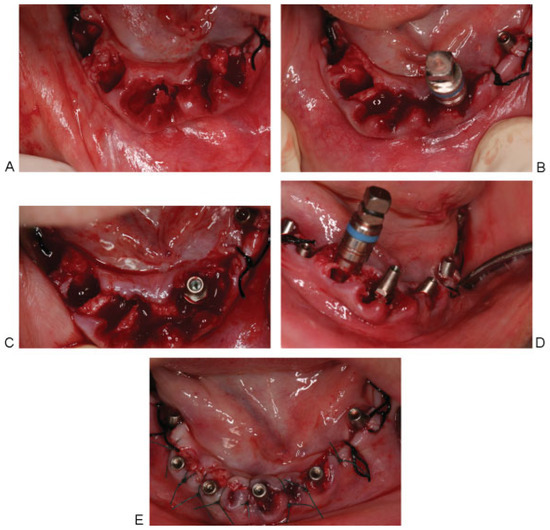

Figure 3. (A) Reflection of the mucoperiosteal flap on the left side and exposure of the alveolar bone, having a width of 2 mm in the premolars area, and 3 mm in the first molar area. (B) Threaded bone expanders no. 2 (color coded, blue) to allow for lateralization of the inferior alveolar nerve and expansion of the resorbed alveolar ridge. (C) The expanders must be maintained in place till the insertion of the implants to avoid collapse of the defect walls. (D) Insertion of two (MRT) implants in the premolars area and bone expander no. 2 in the second molar zone. (E) The three MRT implants in place and suturing back the flap.

The corticotomy was performed in the premolars and first molar area lingual to the crest of the alveolar ridge, using the osteotomy inserts of NSK VarioSurg (NSK, Eschborn, Hesse, Germany), increasing the depth slowly and gradually until it reaches the inferior mandibular cortex. Threaded bone expanders (Microdent implants system, Barcelona, Spain) were then used sequentially to displace the buccal wall, containing the neurovascular bundle, buccally without injuring the nerve, thus atraumatically lateralizing the IAN away from the lingual wall. The expanders also served to prepare the implant bed manually avoiding heat generation by the use of drills. Both the right and left sides received two one-piece implants of 3.85-mm width, 12- and 14-mm length (MRT implants, Microdent implants system, Barcelona, Spain).They were threaded in place with a torque of 40 Ncm. On the left side, in the second molar area distal to the two implants, the pilot drill was used to perform an osteotomy. Bone expanders were used to allow for bone condensation and insertion of another 3.85-mm width, 14-mm length MRT implant. The implant engaged the inferior mandibular border aiming toward a tricortical anchorage (buccal, lingual, and inferior) for greater implant stability. The mucoperiosteal flaps were then sutured back using interrupted and horizontal mattress sutures (Figure 3 and Figure 4).